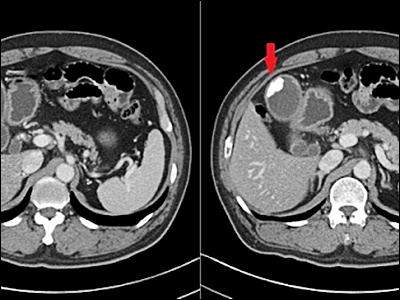

의사는 담낭염을 진단하기 위해 다양한 검사를 시행할 수 있습니다. 가장 일반적인 검사는 혈액 검사와 초음파 검사입니다. 혈액 검사를 통해 염증 마커나 감염 여부를 확인할 수 있으며, 초음파 검사를 통해 담낭의 상태와 담석의 유무를 확인할 수 있습니다. 추가적으로 담도 조영술, CT 스캔, MRI 등의 검사도 시행될 수 있습니다.